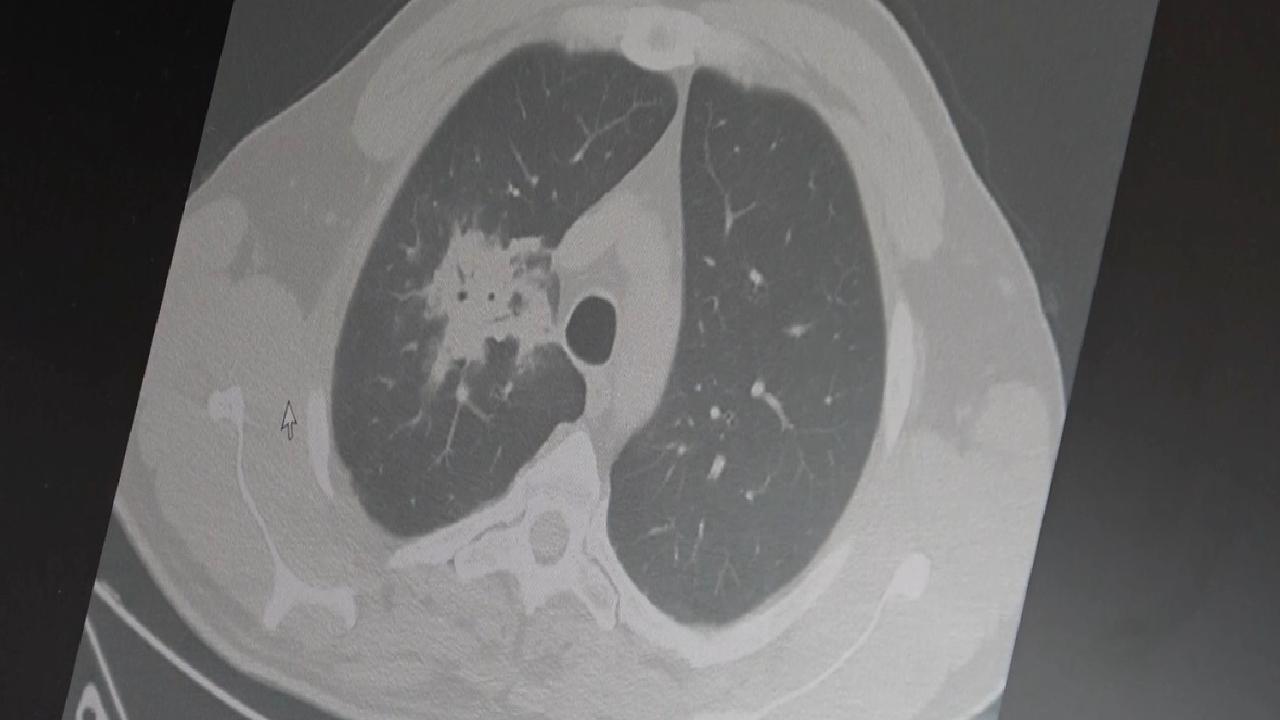

KANSEL RİSKİ VE HÜCRE DÜZEYİNDEN ZARARÖzkaya, 100’den fazla bilimsel çalışmanın incelendiğini ve elektronik sigaraların özellikle akciğer ve ağız çevresinde kanser riskini artırabileceğine dair güçlü emareler bulunduğunu söyledi. Uzun vadeli sonuçlar tam olarak netleşmemiş olsa da erken uyarı işaretlerinin ciddi olduğuna vurgu yaptı. Araştırmalarda insan, hayvan ve laboratuvar verilerinin bir arada değerlendirildiğini belirten uzman, elektronik sigaraların içerdiği kimyasalların hücre düzeyinde zararlar yaratabildiğini ifade etti.

HÜCRE DÜZEYİNDE CİDDİ HASARDNA hasarı, oksidatif stres ve kronik iltihaplanma gibi kanser gelişiminde kritik rol alan üç temel mekanizmanın tetiklendiğini aktaran Özkaya, bu faktörlerin doğrudan kanser oluşumuna zemin hazırladığını kaydetti.

ÇİFTE KULLANIMIN RİSKİ ARTIŞI2024 yılında yayımlanan bir çalışma, hem geleneksel sigara hem de elektronik sigara kullananlarda akciğer kanseri riskinin yalnızca sigara içenlere göre dört kat artabileceğini gösterdi.